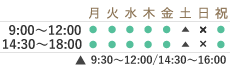

ラミネートベニア

歯の色調の改善や、軽い歯並びの改善(歯のすき間を隠すことも出来ます)のために歯の表面に薄いセラミックを特殊な接着剤で張り付ける治療法です。歯の表面を削る量はほんのわずかです。(状態によっては歯を削らない場合があります)

また治療にかかる期間も数回のご来院で終わります。ご自分の歯の色調が基本となるので、色調の大幅な改善を希望される場合は、ベニア治療の前にホワイトニング治療をお勧めすることもございます。

治療前